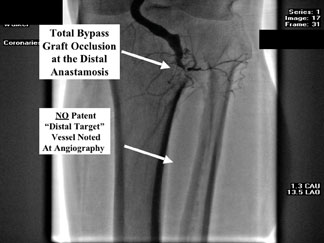

Most patients with diabetes who do suffer from severe infrapopliteal CTOs have the phenomenon of “pedal sparring.” This refers to the fact that the dorsalis pedis artery (DPA) and/or posterior tibial artery (PTA) below the level of the ankle will often be free of obliterative disease. These arteries are patent and be perfused by a collateral artery network, revealing a “distal vascular target” appropriate for revascularization. This presents an opportunity for either surgical or endovascular revascularization.

This becomes very important with committed limb salvage angiography and during CTA. If physicians are not aware of this “pedal sparring,” they will not consider revascularization and their imaging will be inadequate. Patients often receive referrals for primary amputation when they actually have the potential for revascularization.

Femoral–tibial bypass surgery has been and continues to be an excellent therapy. It is indeed a cornerstone in every limb salvage program. Bear in mind that tibial bypass grafts have a 15 to 20 percent attrition rate over 12 to 24 months. Many of our patients today require creative tibial bypass grafts with less than optimal conduits. All endovascular and surgical therapies require close clinical and objective follow-up surveillance.

In my practice, it is common to see a patient in whom we have performed several endovascular therapies over a five- to six-year period of time for limb salvage. The patient would subsequently require a femoral to tibial bypass graft and the next CLI episode would occur after endovascular therapies have failed. Note that 20 to 30 percent of all limb salvage patients will need a second endovascular limb salvage procedure within 18 months. In such patients, the tibial bypass graft will now have an 80 percent patency at approximately 18 to 24 months.

We have learned to perform aggressive graft surveillance and we will often identify graft problems such as kinking, anastomotic intimal hyperplasia, vein graft valve lesions, etc.Vascular interventionalists would then salvage these grafts by utilizing endovascular techniques such as specialty balloons, stents, etc.